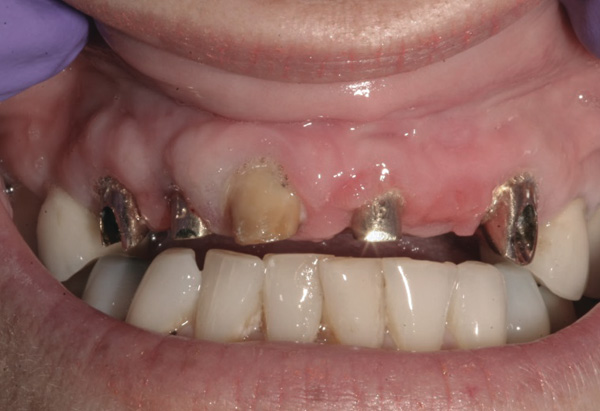

Case 1 – Re-preparing Abutments Intraorally

Background: This patient had a failing maxillary dentition and refused to wear a removable prosthesis. A staged approach was employed to retain some of his natural tooth abutments, and recession was noticed at the time of the impression for the second group of implants. Figure 1 shows the patient following insertion of the first set of implant custom abutments; the adjacent natural teeth are still present to support the provisional bridge. Seven months later, as shown in Figure 2, those first-stage custom abutments exhibited evidence of 1 mm to 3 mm of recession.

Figure 1  Patient following insertion of first set of implant custom abutments.

Figure 1

Figure 2 After 7 months, the first-stage custom abutments exhibited evidence of 1 mm to 3 mm of recession.

Figure 2